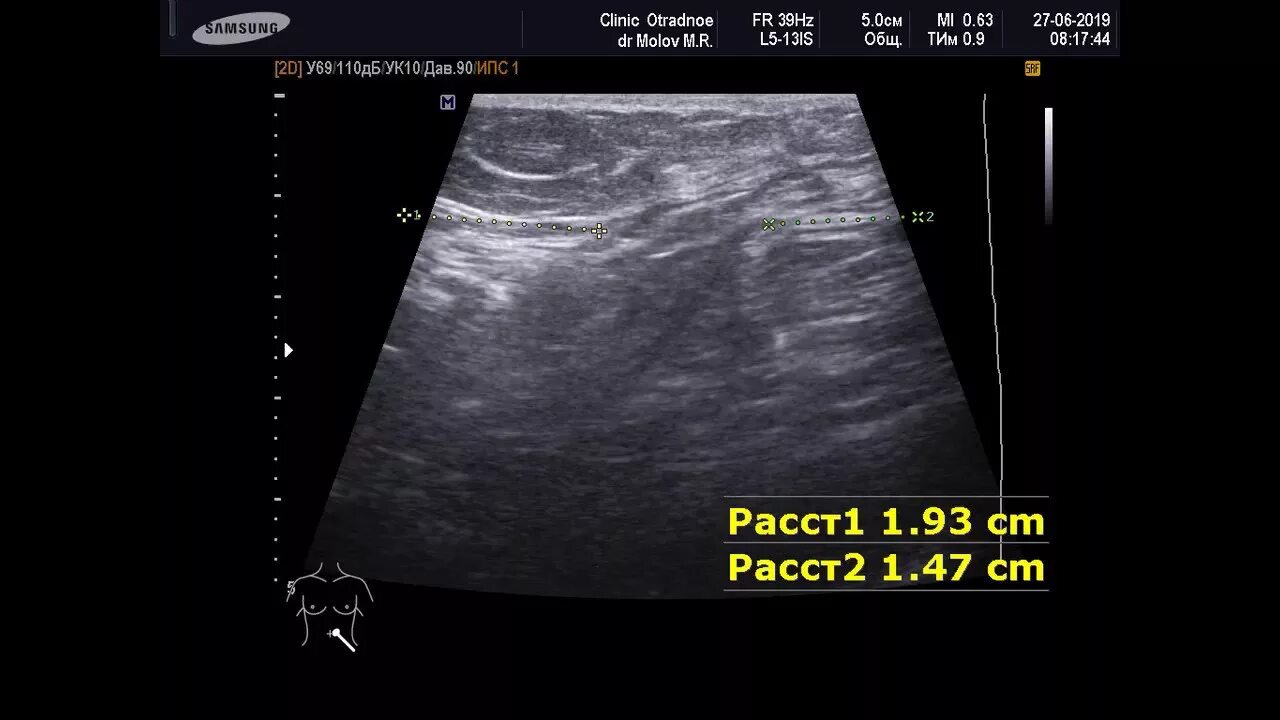

Грыжа спигелиевой линии